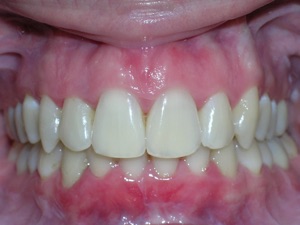

Now for the final results.

Needless to say, we were both quite happy with the outcome. Using elastics we were able to push back the back teeth and create space for the two teeth stuck behind.